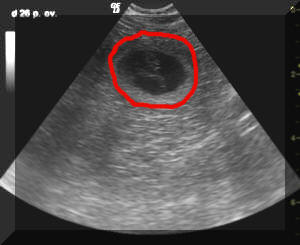

Hier ein paar von den Ultraschallbildern. Die mit rot umrandete Fläche ist ein h in seiner Hülle.